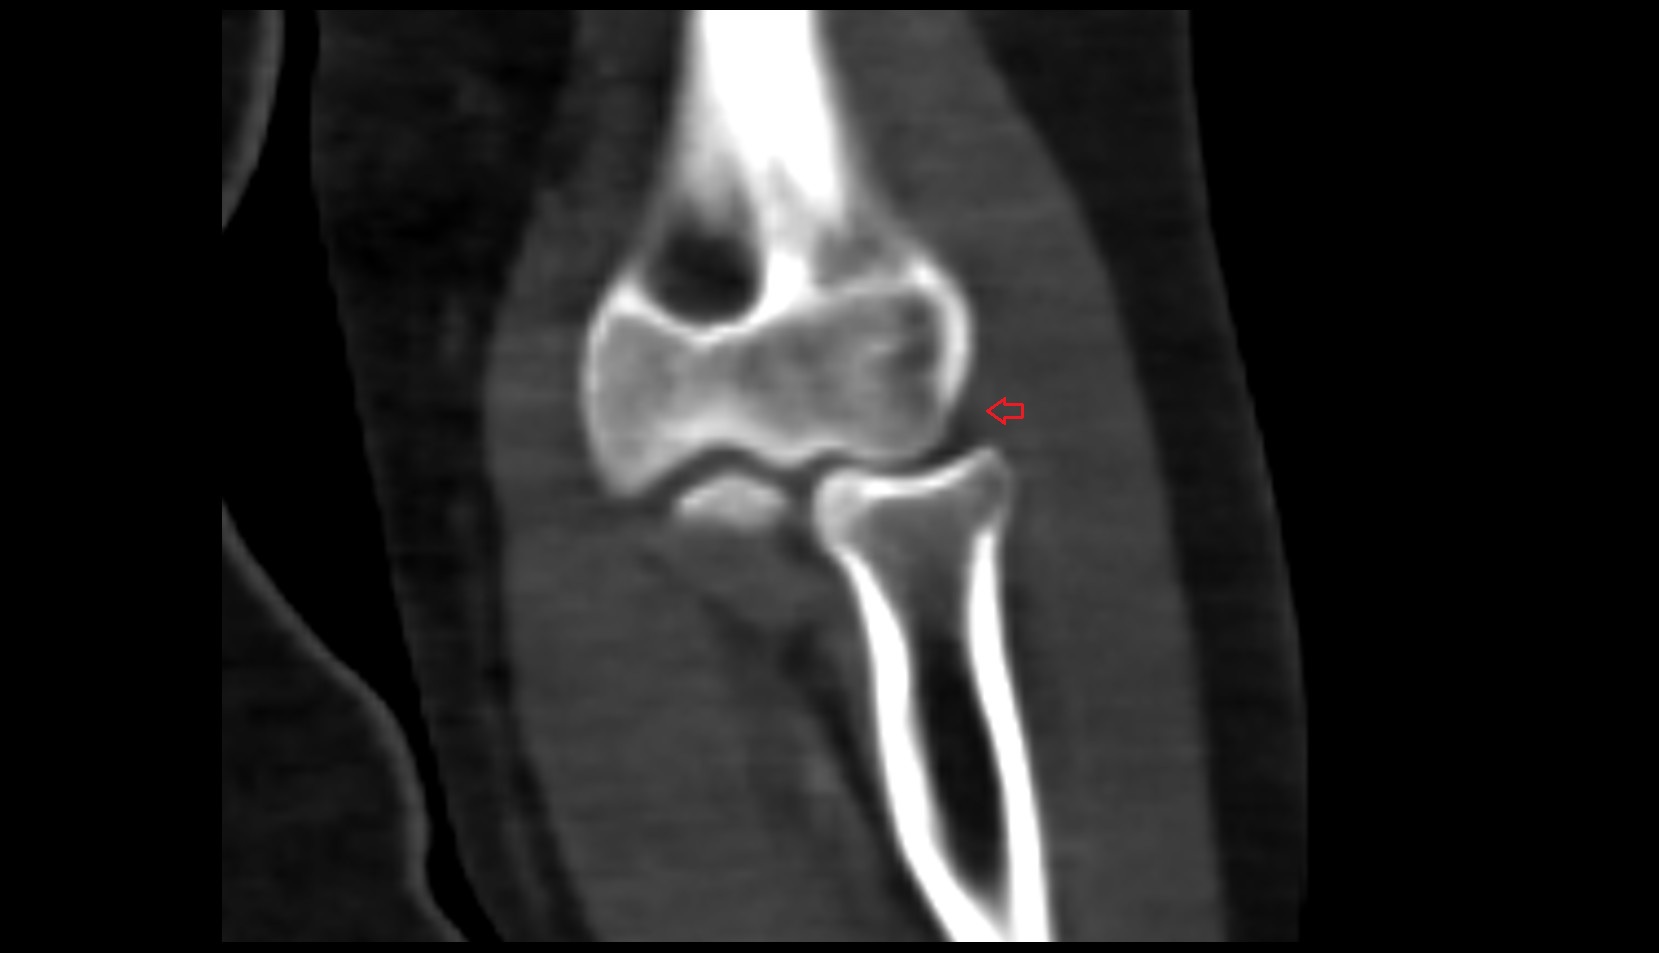

- Knee Joint